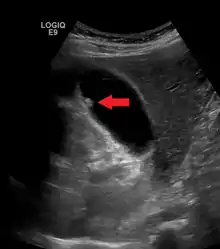

| A polyp in the gall bladder as seen on ultrasound |

Adenomyomatosis describes a diseased state of the gallbladder in which the gallbladder wall is excessively thick, due to proliferation of subsurface cellular layer. It is characterized by deep folds into the muscularis propria. Ultrasonography may reveal the thickened gallbladder wall with intramural diverticulae, called Rokitansky-Aschoff sinuses.[3]

Diagnosis is typically by ultrasound or CT imaging.